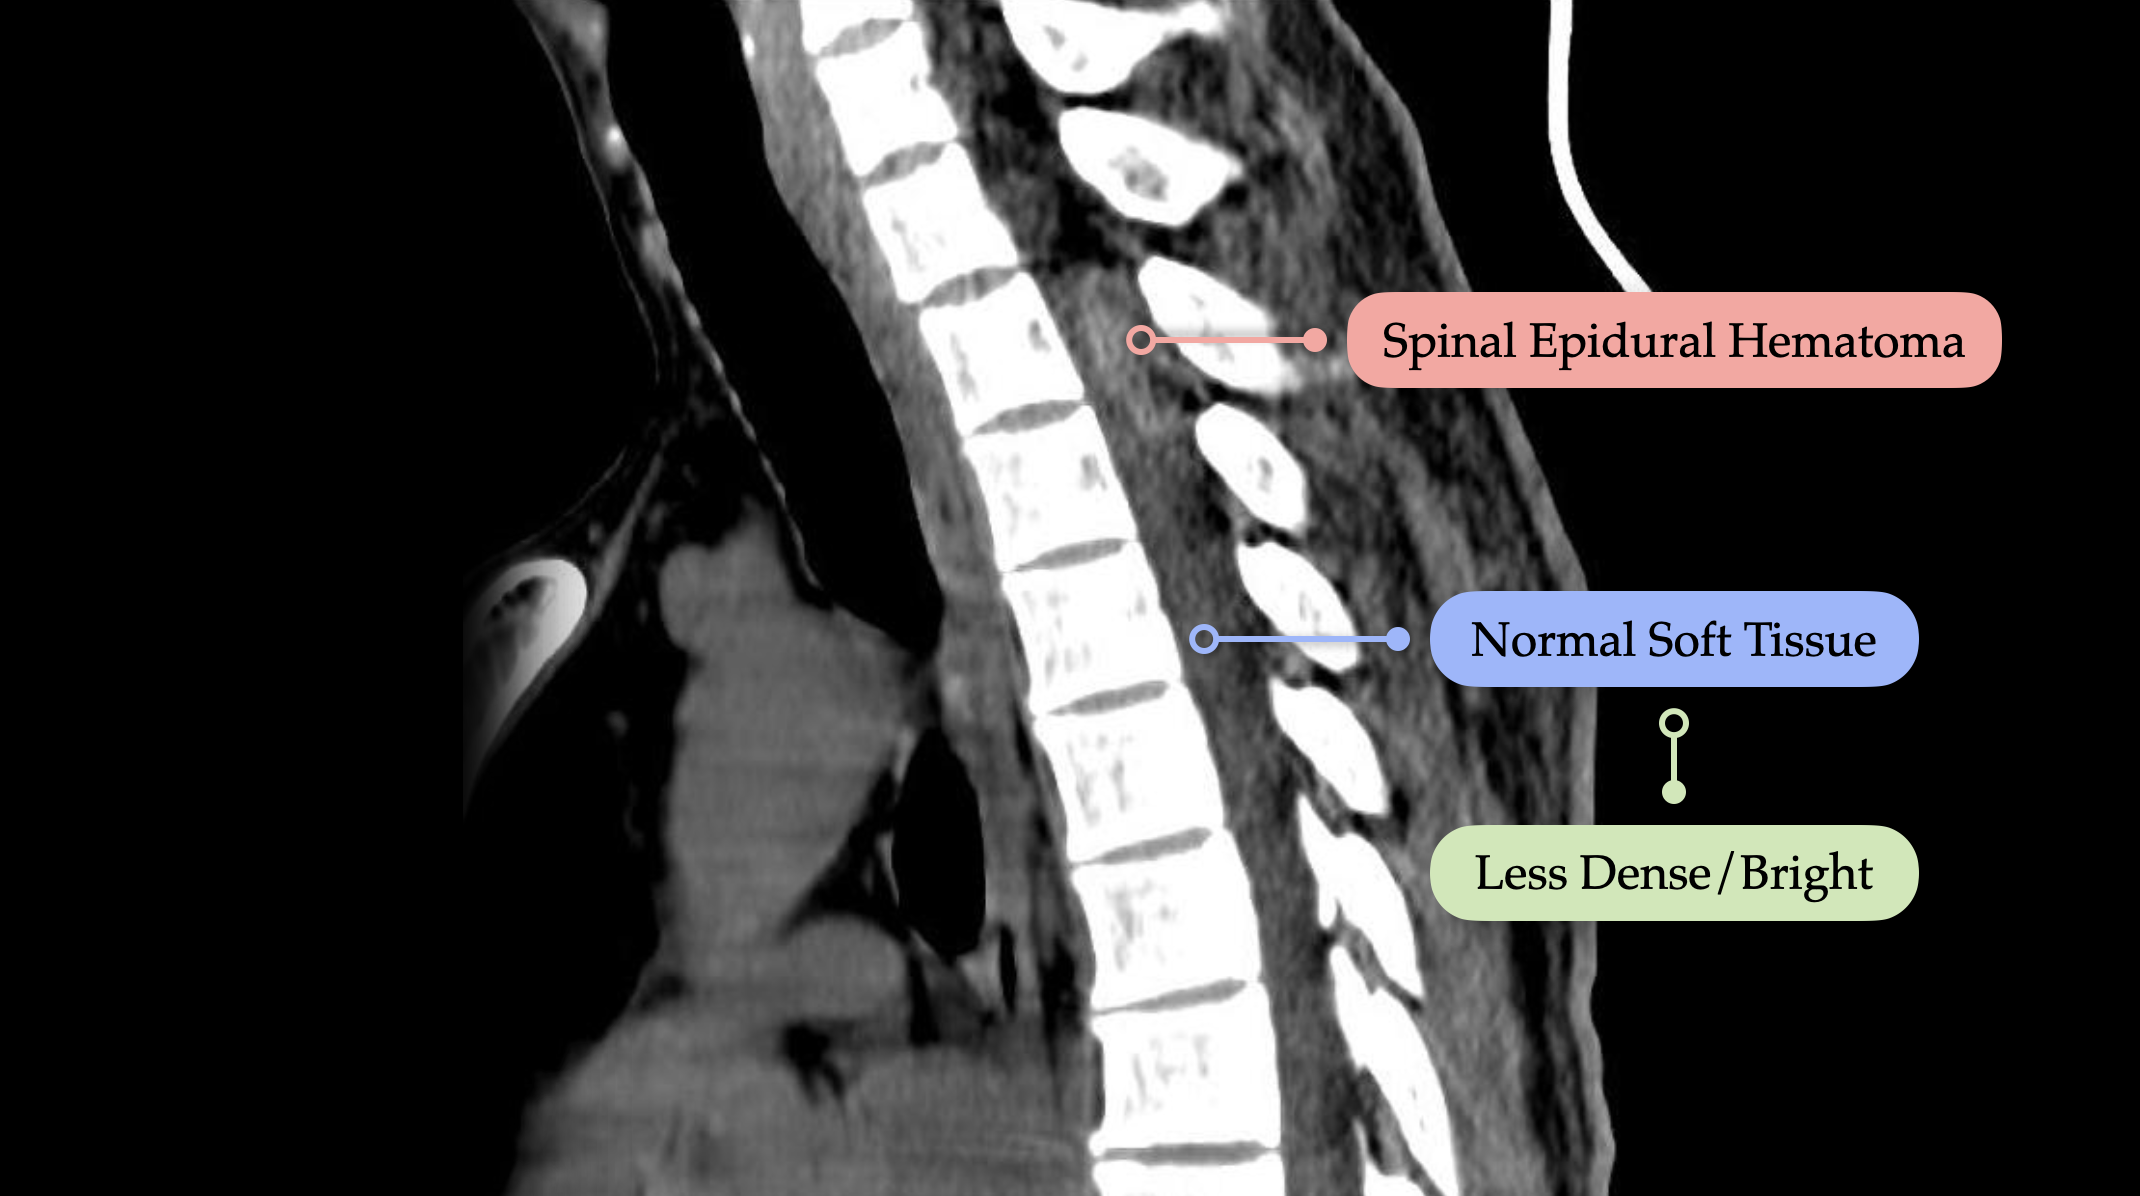

A patient in your department has fallen and is now reporting neck pain with paresthesias in the extremities. They have a known history of apixaban use. This is a classic setup for a spinal epidural hematoma—an easily missed but critical diagnosis.

Key takeaways:

Imaging of choice: Non-contrast CT of the cervical spine

Technique matters: Always review axial, sagittal, and coronal planes

Window settings: Don't rely solely on the bone window—switch to the soft tissue window to identify subtle hematomas, especially in anticoagulated patients.